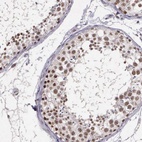

Immunohistochemical staining of human testis shows distinct nuclear positivity in cells in seminiferus ducts.